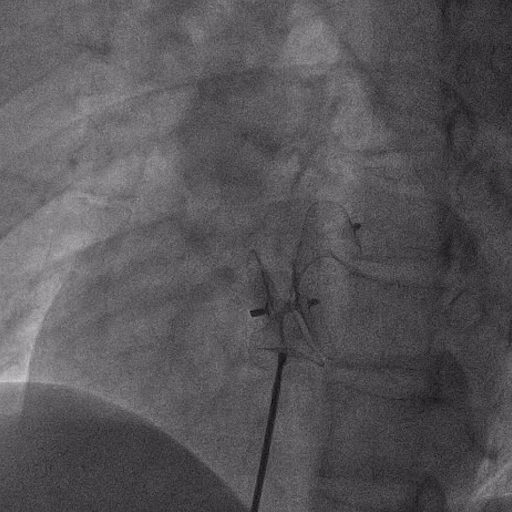

在獲得患者同意后,1月12日,尚福軍主任為患者進(jìn)行了PFO封堵術(shù)。術(shù)中造影可見(jiàn)封堵器殘余漏,尚福軍主任用精湛的技藝,順利通過(guò)封堵器殘余漏裂縫,將右心導(dǎo)管從右房送入左房,且順利到達(dá)肺靜脈;遂行卵圓孔未閉封堵術(shù)后殘余漏再次封堵;且完美釋放PFO封堵器,可見(jiàn)兩封堵器呈“馬蹄蓮”狀,再次術(shù)中造影未見(jiàn)殘余漏。